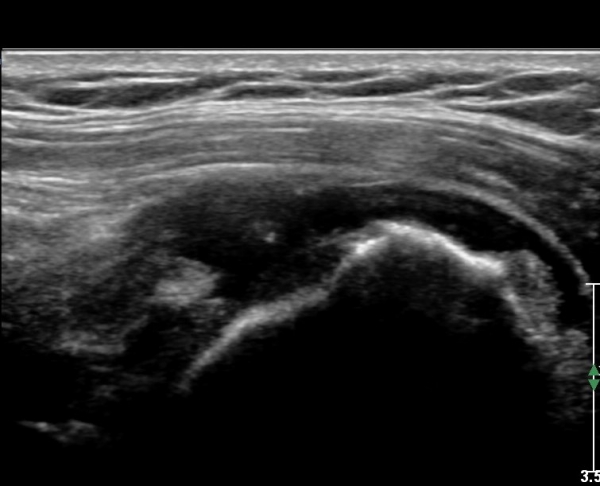

ŽÃËÀÚ¸¦ Á¶±Ý ¸»´ÜÀ¸·Î À̵¿ÇÏ´Ï ¿À±¸µ¹±â°ßºÀÀÎ´ë °ßºÀ ºÎÂøºÎ °ñ±ØÀÌ °üÂûµÇ°í ÀÎ´ë ½ÉÃþºÎ¿¡ ¼ö¾×Àú·ù°¡ ÀÖ¾î ¸¸¼ºÀûÀÎ Ãæµ¹À» ÃßÁ¤ÇÒ ¼ö ÀÖ´Ù(»çÁø 2).